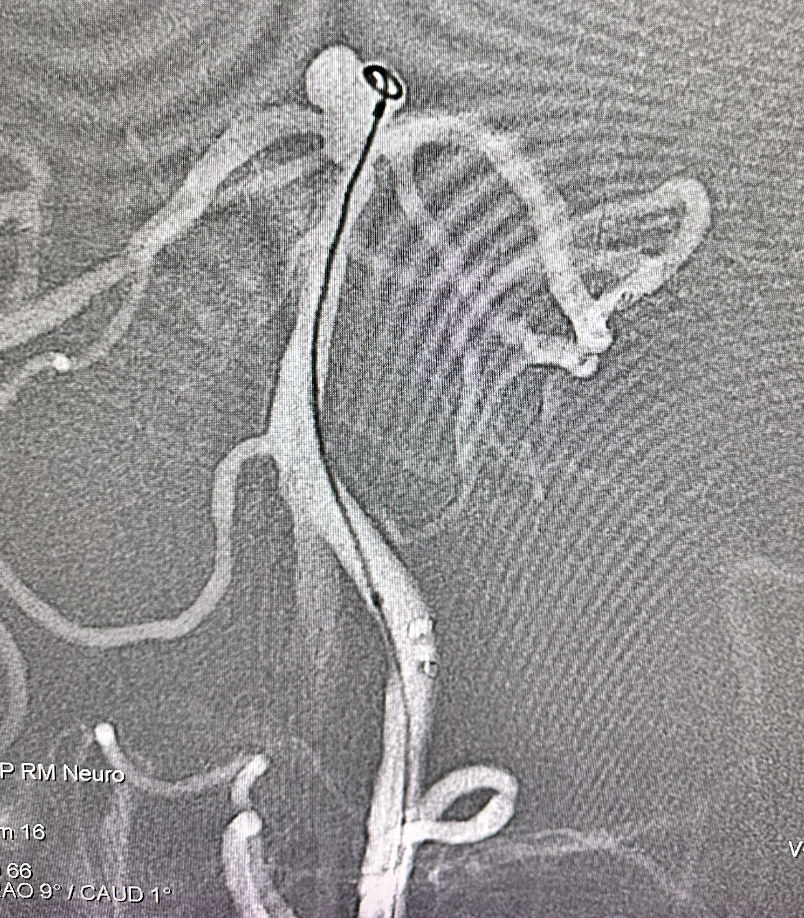

畅医达(TaminoVIA)颅内动脉瘤辅助栓塞支架完全释放,打开效果好,显影清晰,瘤体部分显影

患者高龄,瘤体破裂出血风险降低,考虑编织支架修复作用,未继续填塞弹簧圈

术后造影显示动脉瘤囊闭塞,畅医达(TaminoVIA)颅内动脉瘤辅助栓塞支架形态良好,载瘤动脉通畅